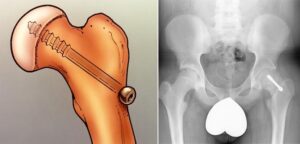

Open Reduction

For patients with unstable SCFE, a more extensive surgical procedure called open reduction may be required. In this approach, the surgeon makes a larger incision in the hip and carefully manipulates the femoral head back into its correct anatomical position. After repositioning the femoral head, one or two metal screws are inserted to secure the bone and maintain proper alignment until the growth plate naturally fuses. While this procedure effectively restores hip stability, it is more complex and involves a longer recovery period compared to other treatment methods.

(Left) Preoperative X-ray of an unstable SCFE . (Right) Postoperative X-ray shows that the femoral head has been manipulated back into place and screws have been inserted to hold it in place.

Illustration and X-ray of in situ fixation. A single screw is inserted to prevent any further slip of the femoral head through the growth plate.